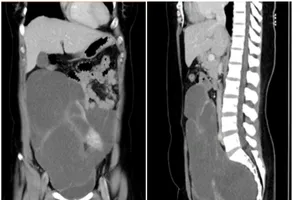

Đi tiểu nhiều, đi khám mới hay khối u 2,8 kg ở vùng chậu